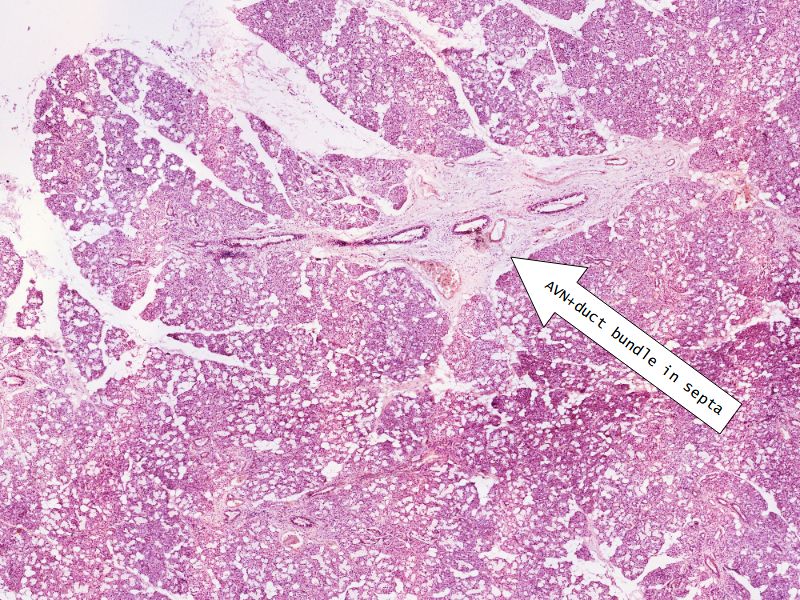

Fill in all the missing labels, and assess as you move through the slides. Answers on the down slide. It is important to do this using pen and paper, and not just glance through the images.